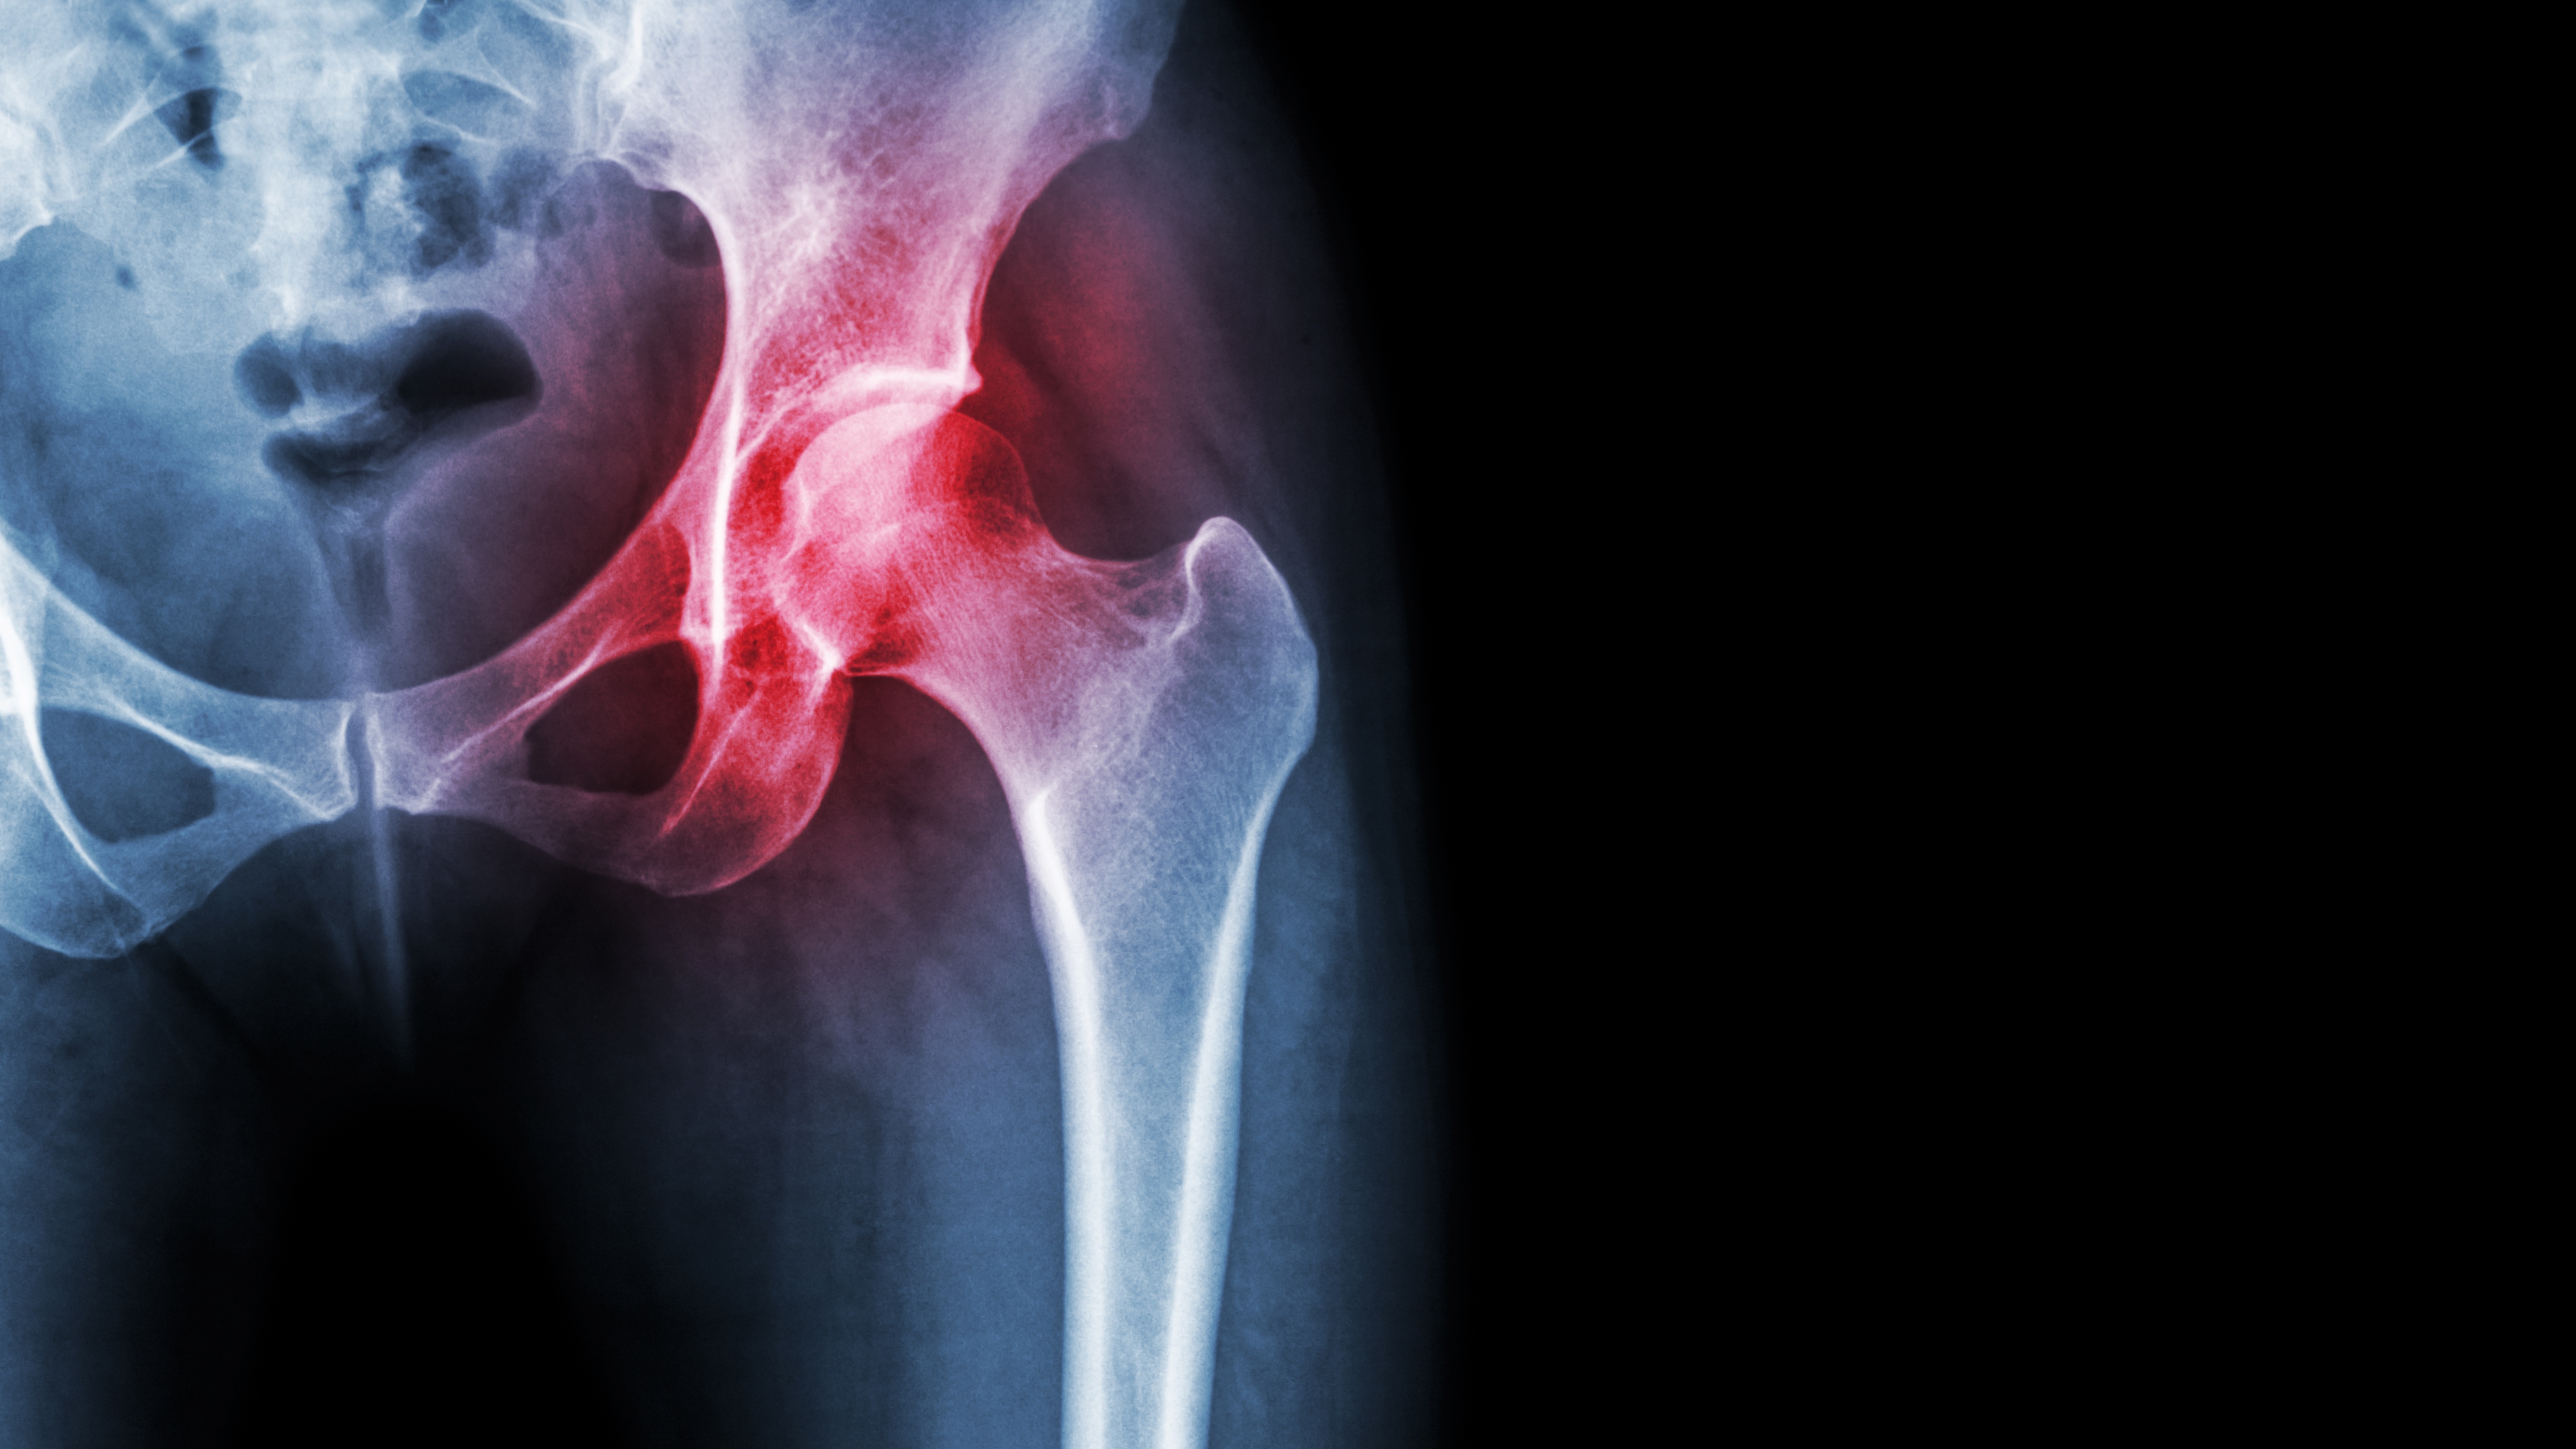

Certain Subsets of Older Patients With Pelvic Ring Injuries Benefit From Surgery .

Certain subsets of older adults with pelvic ring injuries may benefit from surgical treatment, particularly when fractures are unstable or significantly painful. In older patients, pelvic ring injuries often result from low-energy trauma and can be associated with serious mobility loss and complications if managed nonoperatively. Newer approaches — especially minimally invasive surgical fixation — are increasingly used in selected patients to reduce pain, promote earlier mobilization, and improve functional outcomes compared with nonoperative care. However, clinical practice varies widely, and definitive evidence about exactly which patient groups benefit most from surgery is still evolving. These decisions typically depend on fracture pattern, overall health status, and the patient’s ability to tolerate surgery, underscoring the need for more standardized treatment protocols.